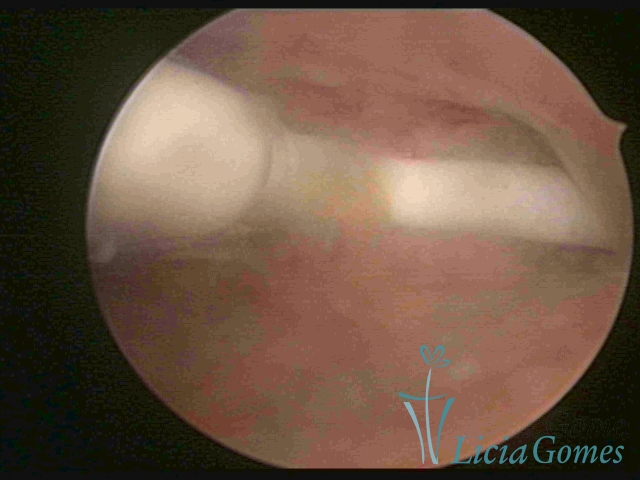

Normoinserted IUDo

Normoinserted IUD